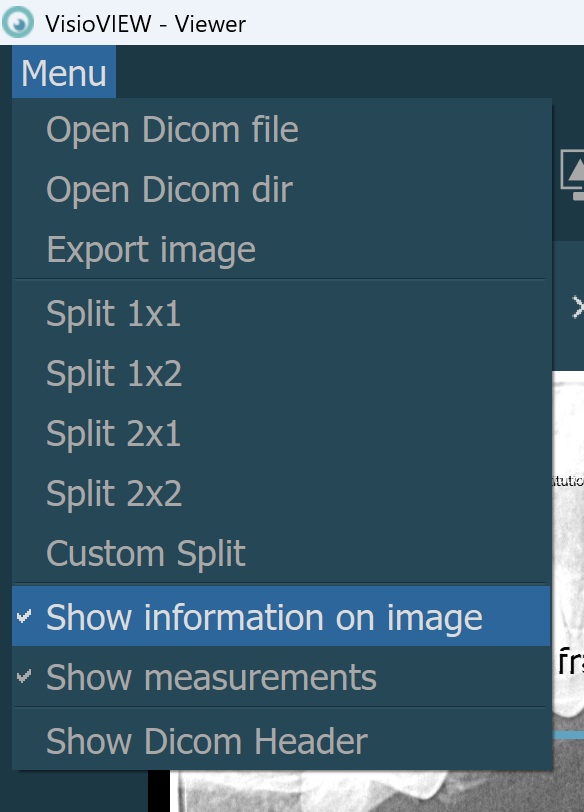

To toggle whether the information displayed on the images is visible, use the Menu -> Show information on image option from the VisioVIEW Viewer.